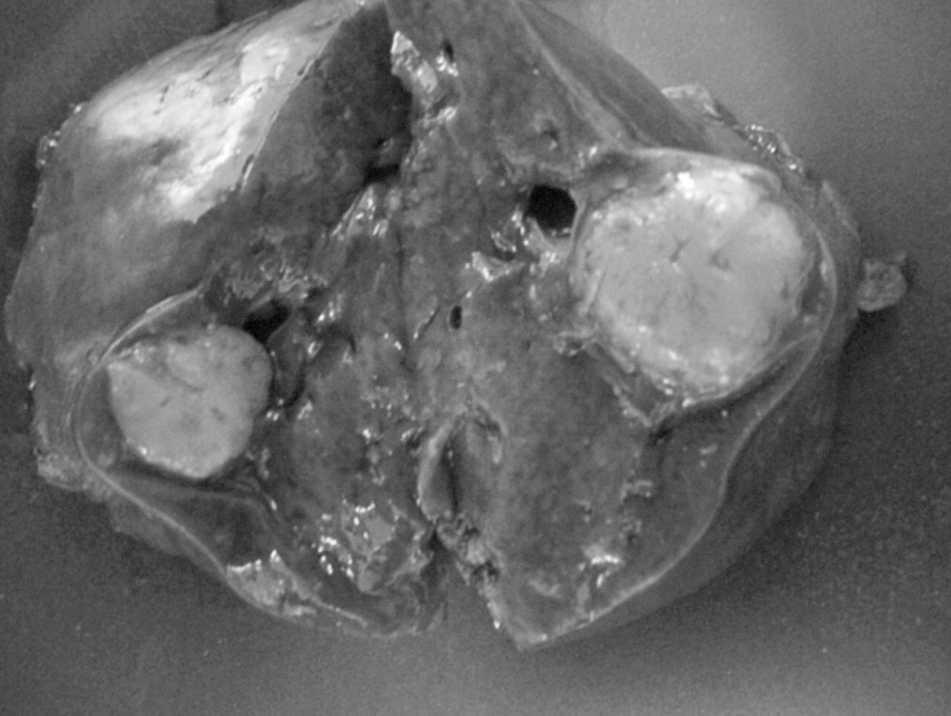

Mujer de 33 años, sin antecedentes médicos de interés, de origen magrebí. La paciente estaba asintomática. Hallazgo casual, por ecografía realizada por trastorno ginecológico, de una lesión ocupante de espacio en el segmento VI hepático confirmada por tomografía computarizada y resonancia magnética (RM) (fig. 1). Diagnóstico: masa hepática hipoecogénica en segmento VI con una ligera hiperseñal en secuencia T2 y un resalte periférico en la fase arterial tras la inyección de gadolinio. A pesar de que no se evidenció crecimiento de la lesión en una RM realizada a los 3 meses, se procedió a su extirpación quirúrgica. La punción-biopsia no fue concluyente, en ausencia de material adecuado. El hemograma fue normal: hemoglobina, 13,5; hematocritos, 40%; leucocitos, 7.020 con el 8,6% de linfocitos. La bioquímica sérica mostró los siguientes valores: proteínas totales, 5,8; colesterol, 104 mg/dl, lipoproteínas de baja densidad, 43,8 mg/dl; GOT, 288; GPT, 337; alfafetoproteína, 1,8 U/ml; CEA, 1,6 ng/ml; CA 19.9, 11,7 U/ml. Se descarta de entrada adenoma, hepatoma, colangiocarcinoma e hiperplasia nodular focal. Decisión terapéutica: segmentectomía del VI (fig. 2). Informe anatomopatológico: hiperplasia nodular linfoide hepática de 1,5 cm con márgenes quirúrgicos libres de infiltración tumoral (fig. 3); el resto del parénquima era de carácterísticas normales. A los 24 meses, la paciente está viva, en buen estado general y libre de enfermedad.

Fig. 2. Pieza de resección.